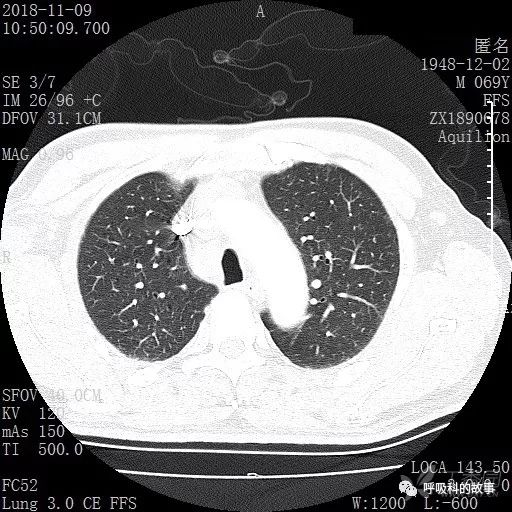

胸部增强CT示右肺门占位伴远端阻塞性肺炎,纵膈、右肺门、右侧颈根部、右侧腋下及肝门部肿大淋巴结。两侧胸腔少量积液。

肺窗CT